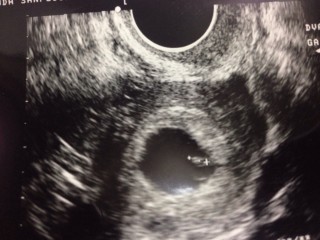

小さいほうが4w6dのときで胎嚢のみ確認できました。

大きいほうが5w6dのときで卵黄嚢確認。

来週あたりに胎芽と心拍確認できる予定です。